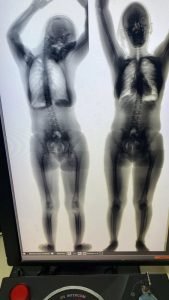

A droga foi detectada pelo body scan (escâner corporal), equipamento utilizado para identificar drogas, armas e outros objetos considerados ilícitos dentro de uma unidade prisional ou em qualquer outro ambiente protegido.

Após a detecção do entorpecente, ela foi conduzida para a sala de extração (sendo o produto extraído pela própria conduzida), foi comprovado que o corpo estranho era maconha.